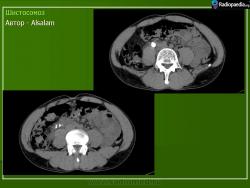

Бильгарциоз (Schistosomiasis) мочевого пузыря